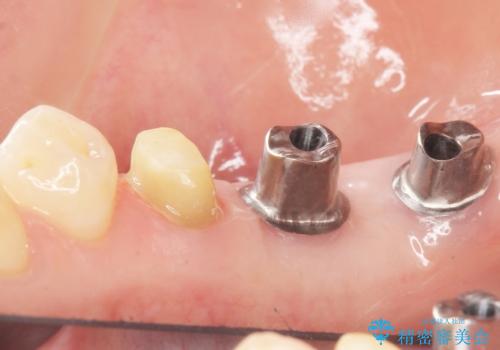

患者様のご希望により、右下大臼歯2本(右下76)のインプラント治療、右下小臼歯(右下5)の根管治療及び補綴治療を行いました。

割れていた歯の周囲組織の炎症が強く、骨の厚みが薄かったため、インプラント埋入時に骨増生(GBR)を行いました。

インプラントの種類:ストローマン BLT